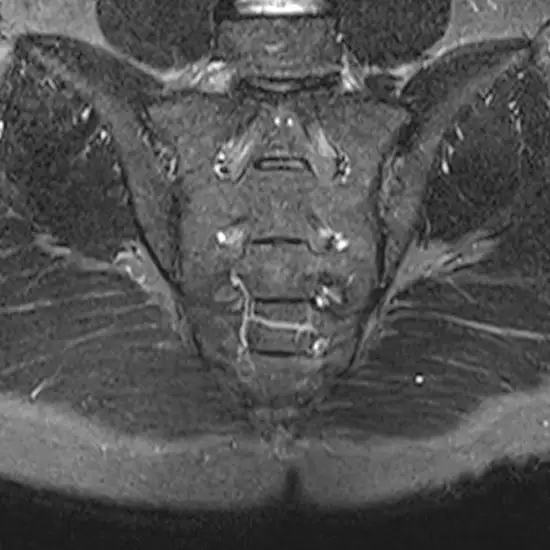

MRI of the sacroiliac (SI) joints is a magnetic imaging technique used to provide a detailed image of the SI joint, which is the joint that connects the hip bones to the sacrum (joint present at the base of the spine).

This test is used to determine whether a joint has ankylosing spondylitis. It aids in assessing the size and structure of the swelling. The structural changes associated with inflammation are easily detected by MRI, which can also assess correct identification and treatment.